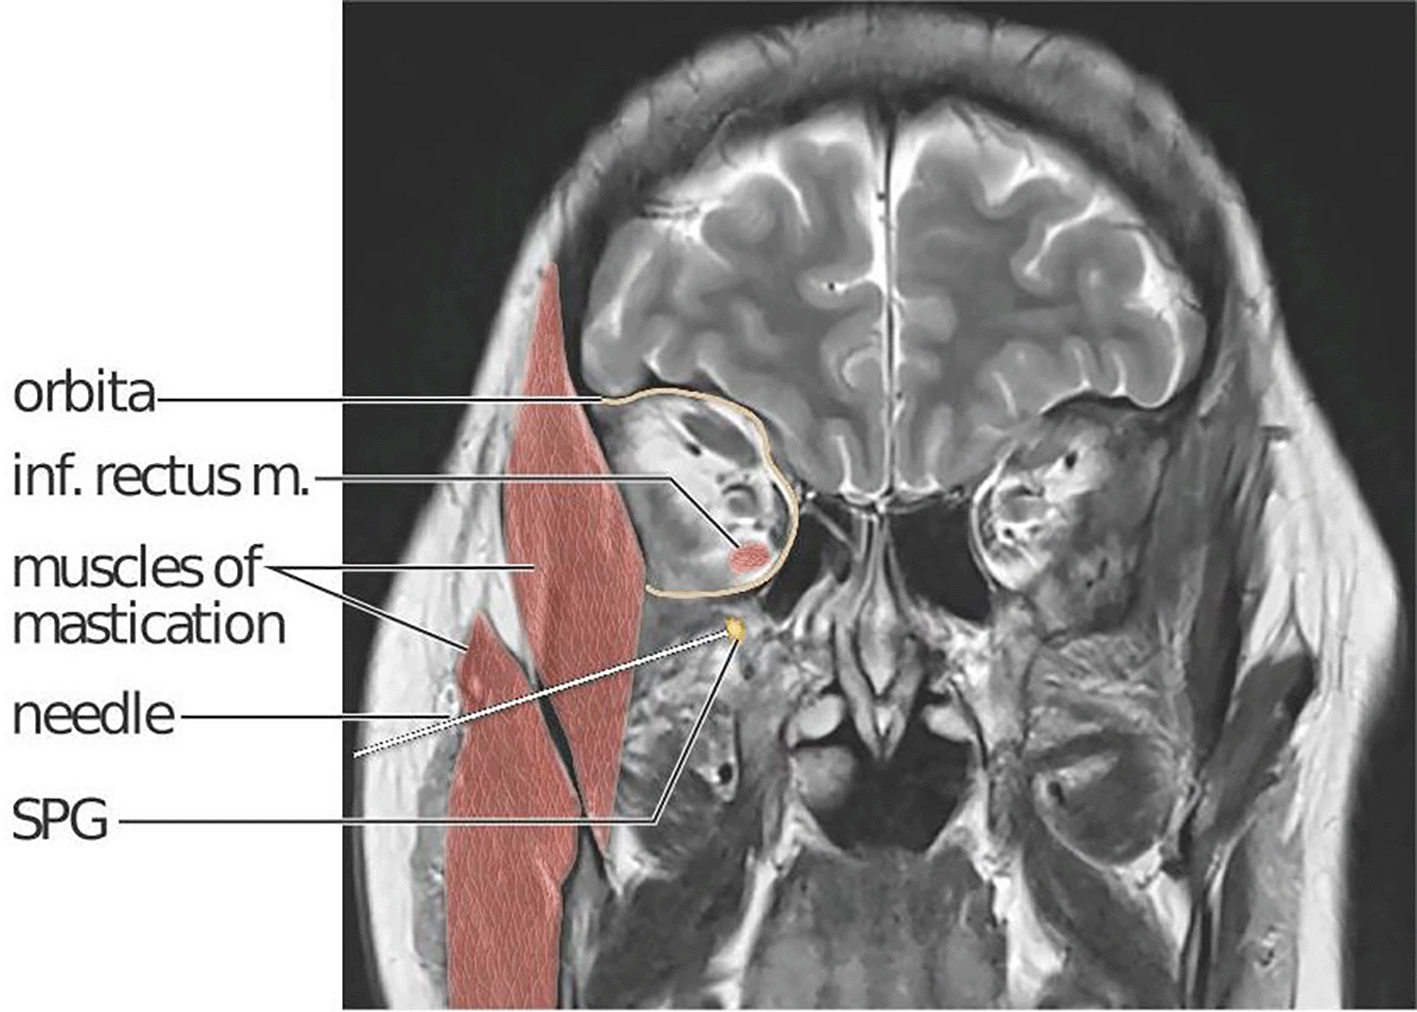

In 1909, Sluder published the first report of treatment targeting the SPG, using intranasal administration.11 More than a century later, only a limited number of studies exploring SPG-targeting interventions such as nasal lidocaine or bupivacaine and electrical or radiofrequency stimulation, exist.12 Two randomised controlled studies on SPG stimulation in chronic cluster headache are published, demonstrating efficacy in aborting cluster headache attacks.13,14 The intervention requires surgery for device implantation and the device is currently not available. In chronic migraine, transnasal bupivacaine administration is the only SPG-targeting therapy studied in a blinded and placebo-controlled design.12,15,16 The location of the SPG within the sphenopalatine fossa, situated deep within the facial structures behind the maxillary sinuses ( Figure 2), presents challenges for a non-invasive pharmacological treatment strategy targeting the SPG. The distance between the nasal mucosae and the SPG is a major obstacle for all methods applying non-invasive, intranasal administration.17 The MiBlock trial addresses this challenge by employing a navigation-guided injection procedure to secure high precision targeting. The procedure can be performed in an office-based setting under local anaesthesia, utilizing a lateral (percutaneous) access rather than a transnasal approach. The procedure was piloted in an open-label, phase 2 study on treatment- resistant chronic migraine. Bilateral onabotulinumtoxinA injections in 10 participants were deemed safe and secondary migraine-related outcome measures were promising.18 Indeed, eight out of 10 participants reported at least 50% reduction of moderate and severe headache days compared to baseline. Recently published real-world data on repeated treatments also provides favourable safety and efficacy data.19

A needle penetrates skin and subcutaneous tissue, the masseter and temporal masticatory muscles (red) and ends at the right SPG (yellow). The SPG is located in the sphenopalatine fossa, just below the orbital (delineated in yellow). The sphenopalatine fossa and orbita communicate via the inferior orbital fissure. The inferior rectus muscle is highlighted to show the close anatomical relation between its orbital insertion and the location of the SPG. Kari C Toverud owns the copyright to the image. Printed with permission from © Kari C. Toverud.

The interventional procedure in MiBlock is a single session, bilateral, percutaneous injection towards the SPG performed using the MultiGuide® device aided by image-guided navigation. The MultiGuide® is a novel medical device developed by the research group from St. Olav’s Hospital and NTNU and holds a CE-label for the procedure. A commercially available surgical navigation system is used to plan an injection trajectory and provide real-time guidance of needle placement. The needle entry can either be supra- or infrazygomatical, depending on which trajectory provides best access to the sphenopalatine fossa. An example of an infrazygomatical trajectory is illustrated in Figure 2.